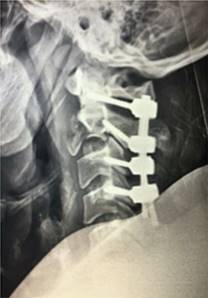

El paciente fue sometido a biopsia transpedicular abierta del cuerpo de C2 y artrodesis cervical mediante instrumentación posterior de C1 a C4 (Figura 4). Como complicación transoperatoria el paciente sufrió lesión de la membrana occipitoatloidea, lo que condicionó una fistula de líquido cefalorraquídeo que requirió reintervención posterior por parte del servicio de neurocirugía, reparada mediante sustituto de duramadre, además desarrolló infección del sitio quirúrgico por E. faecalis multirresistente, la cual se resolvió mediante antibioticoterapia. Posteriormente el paciente egresó y se realizó seguimiento en la consulta externa.